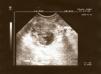

En la ecografía transvaginal se visualizaba un útero en anteflexión de 73 x 41mm con un endometrio lineal de 5,3mm. En el anejo derecho se observaba una formación econegativa de 16mm y en su interior dos embriones, con latido cardíaco positivo en ambos (fig. 1); el anejo izquierdo era normal. No se objetivó líquido libre en fondo de saco de Douglas. El hemograma y la bioquímica se encontraban dentro de los parámetros normales.

En nuestro caso no fue necesario determinar la concentración sérica de β-HCG, ya que en la ecografía se pudo identificar claramente un útero vacío junto a una formación eco negativa de 16mm en el anejo derecho dentro del cual se vieron dos embriones con latidos identificables.